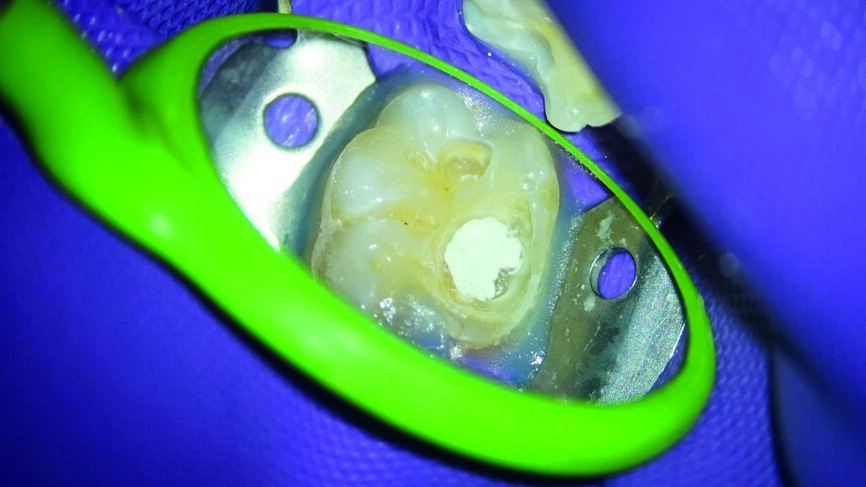

Ein 24-jähriger Patient kam mit vorübergehenden, provozierten Zahnschmerzen an Zahn #19 in die Zahnklinik (Abb. 1). Die Diagnose lautete reversible Pulpitis. Die Zahnfäule wurde unter kompletter Isolation entfernt, wobei es zweimal zur Freilegung der Pulpa mit minimalen Blutungen kam (Abb. 2). Die Blutungen wurden gestoppt, indem 10 Sekunden lang ein mit steriler Salzlösung getränkter Wattebausch auf die Stelle gedrückt wurde. Die Mundhöhle wurde mit 2,5% Natriumhypochlorit desinfiziert (Abb. 3), anschliessend wurde weißes MTA (Produits Dentaires) als Mittel zur unmittelbaren Pulpa-Überkappung eingesetzt (Abb. 4). Um sicherzustellen, dass das MTA korrekt eingesetzt wurde, kam das MAP-System für Dentalmaterialien (Produits Dentaires) zur Anwendung. Mit diesem System kann der Klinikarzt das Material exakt an der Expositionsstelle anbringen. Somit wird eine Verunreinigung der Dentinwände verhindert, die mit der Zeit eine Pigmentierung infolge des verwendeten Materials aufweisen könnten (Abb. 5 und 6). Sobald das MTA auf die Expositionsstellen der Pulpa und die tieferliegenden Teile des Pulpakammerdachs aufgetragen wurde, kam eine lichthärtende Kalziumhydroxidpaste zum Einsatz, um das Material zu schützen (Abb. 7), das Klebeverfahren durchführen und die abschliessende Zahnreparatur in derselben Sitzung vornehmen zu können (Abb. 8 und 9). Sieben Tage nach dem Verfahren war der Patient komplett symptomfrei und der Zahn reagierte normal auf Sensitivitätstests. In solchen klinischen Situationen ist davon auszugehen, dass zwischen sechs und neun Monaten nach dem Verfahren die Bildung von Kalkgewebe unter dem Überkappungsmaterial in Röntgenaufnahmen nachgewiesen werden kann. (7)